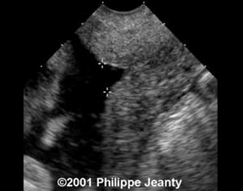

- Đo thể tích tinh hoàn: Sử dụng mặt cắt dọc để đo chiều dài và chiều cao tinh hoàn và mặt cắt ngang để đo chiều rộng của tinh hoàn. Thể tích tinh hoàn: được tính theo công thức của Lambert[6]:

Vtinh hoàn (cm3)= chiều dài x chiều rộng x cao x 0,71

Phân bố đối tượng nghiên cứu theo thể tích tinh hoàn đo bằng siêu âm

Bảng 3. Phân bố đối tượng nghiên cứu theo thể tích tinh hoàn đo bằng siêu âm

(*) Test t không ghép cặp

Thể tích tinh hoàn phải và trái đo bằng siêu âm lần lượt là 9,3±7,9 cm3 và 9,6±8,0 cm3. Thể tích trung bình hai tinh hoàn trên siêu âm là 9,4±8,0 cm3.

Sự khác biệt giữa thể tích tinh hoàn phải và trái chưa có ý nghĩa thống kê (p>0,005)

Sự tương quan giữa thể tích tinh hoàn đo được trên lâm sàng và trên siêu âm

Biểu đồ 1. Sự tương quan giữa TTTH đo được trên lâm sàng và trên siêu âm

Thể tích tinh hoàn đo bằng thước Prader tương quan thuận mạnh với thể tích tinh hoàn đo bằng siêu âm (r=0,840, p<0,0001).